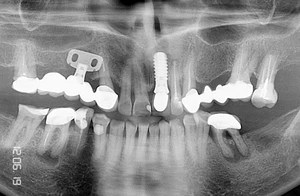

Контрольная рентгенограмм через 15 лет после операции. Если на рентгенограмме и можно различить небольшую щель между имплантатом и костью на уровне полированной части имплантата, то клинически она полностью отсутствует и не диагносцируется парадонтологическим зондом.